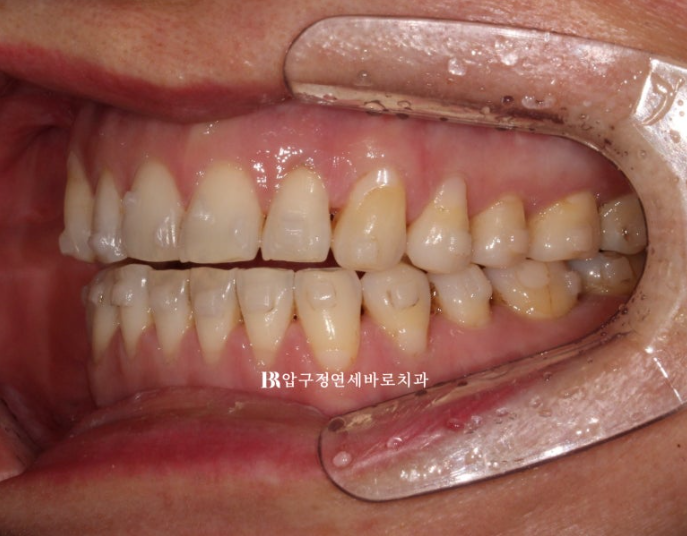

23.05~23.12

걱정하시는 교합도 잘 마무리 되었습니다.

추가장치의 목적은 미세하게 안 맞는 중심선을 맞추고 교정 후 어느정도 재발될 것을 예상해서 살짝 과개교합 상태를 만들어 놓는 것입니다.